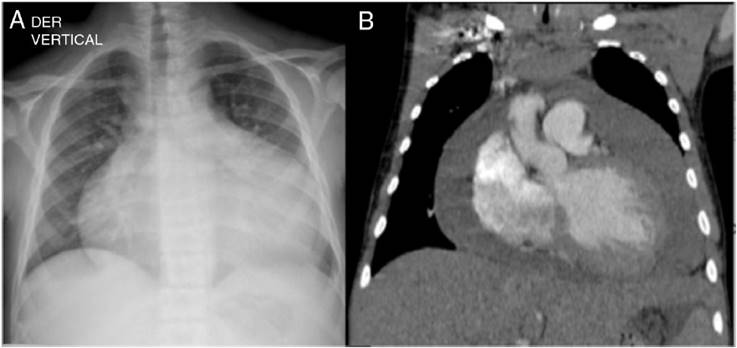

Figura 3 Radiografía postero-anterior (A) y tomografía contrastada de tórax con reconstrucción coronal (B), en la que se observa que el aumento de la silueta cardíaca que se evidenció en la radiografía corresponde en realidad a acumulación de líquido en el pericardio y no a crecimiento de las cavidades cardíacas.